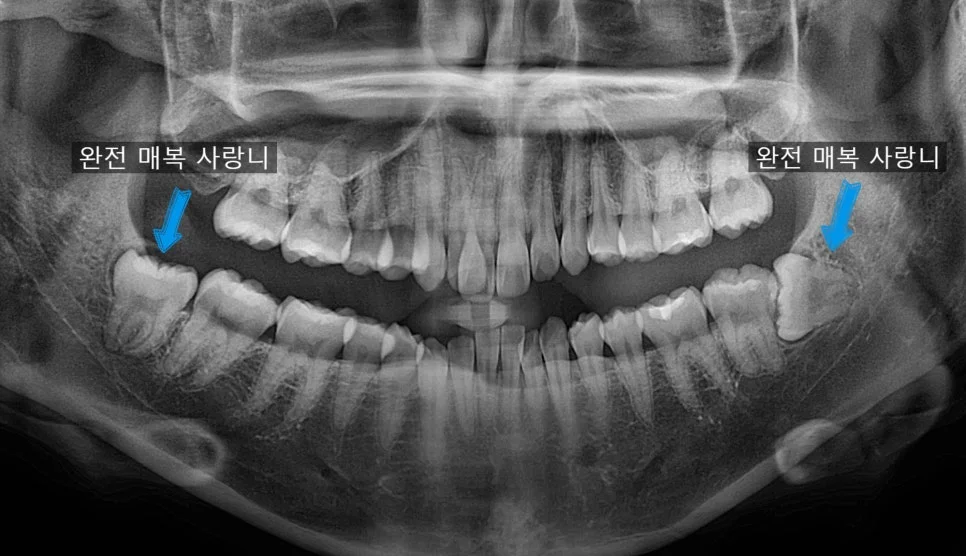

사랑니 4개 발치 전 파노라마 엑스레이 진단 사진

좋은 진료를 정직하게 | 선한 영향력으로 더 나은 가치를 사랑니 4개 한번에 발치, 정말 가능할까? 덜 아프게 뽑는 비결 공개 강서구 마곡 꿈꾸는 쏙쏙 치과의사 박상억입니다. 안녕하세요^^ “하루에 사랑니 4개를 다 뽑으면 너무 아프지 않을까?” “하루에 다 뽑으면 밥은 어떻게 먹죠?” “사랑니 발치 후 술, 담배 가능한가요?” 오늘은 왼쪽 위 사랑니가 붓고 아파서 내원하셨다가, “마취한 … 더 읽기